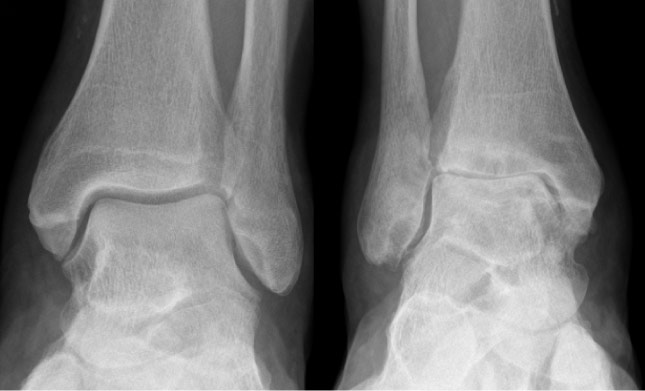

Διάγνωση

Η διάγνωση γίνεται από την κλινική εξέταση και από τις απλές ακτινογραφίες σε φόρτιση.